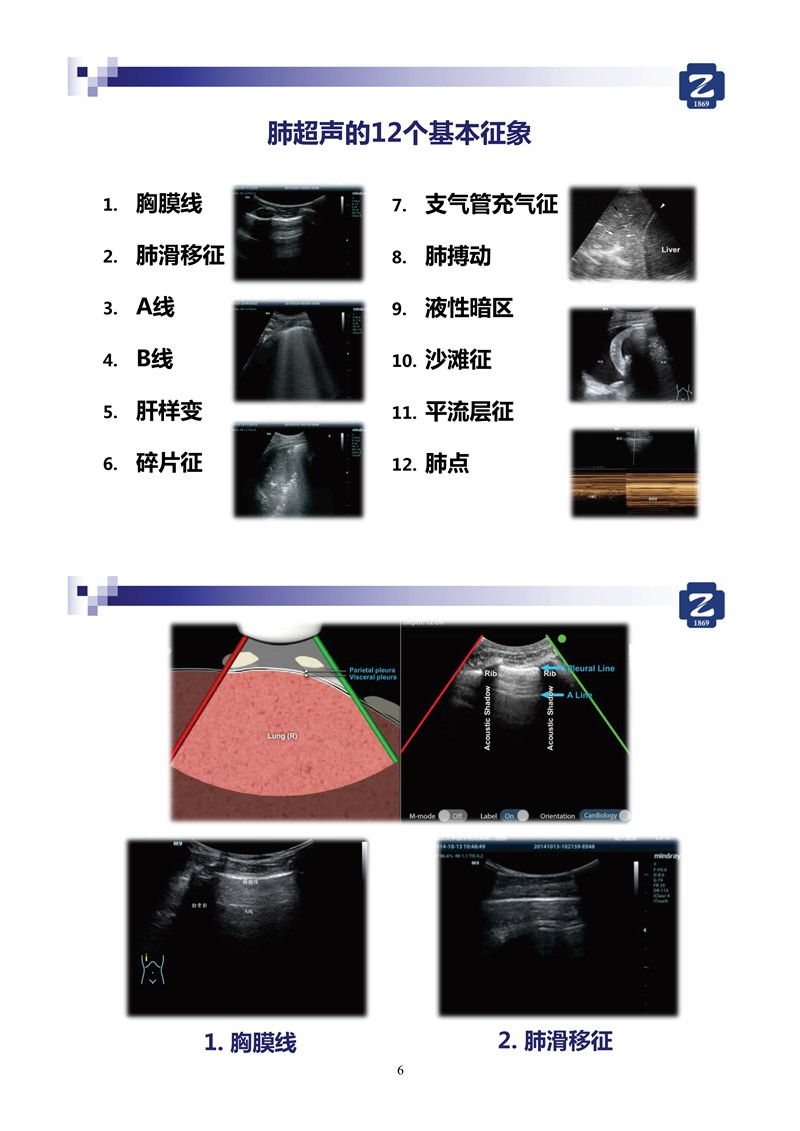

第一版新型冠狀病毒肺炎超聲診斷實用手冊(全文)

新冠肺超聲實用手冊(2)_35.jpg